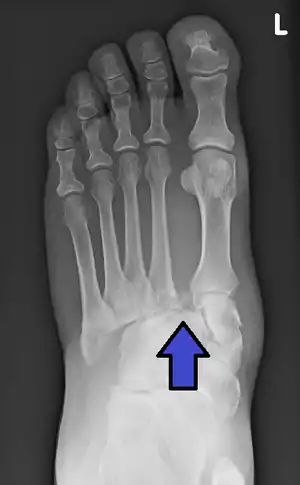

| An X-ray of a Lisfranc injury showing widening between the 1st and 2nd metatarsal base. | |

In a high energy injury to the midfoot, such as a fall from a height or a motor vehicle accident, the diagnosis of a Lisfranc injury should, in theory at least, pose less of a challenge. There will be deformity of the midfoot and X-ray abnormalities should be obvious. Further, the nature of the injury will create heightened clinical suspicion and there may even be disruption of the overlying skin and compromise of the blood supply. Typical X-ray findings would include a gap between the base of the first and second toes.[10] The diagnosis becomes more challenging in the case of low energy incidents, such as might occur with a twisting injury on the racquetball court, or when an American Football lineman is forced back upon a foot that is already in a fully plantar flexed position. Then, there may only be complaint of inability to bear weight and some mild swelling of the forefoot or midfoot. Bruising of the arch has been described as diagnostic in these circumstances but may well be absent.[11] Typically, conventional radiography of the foot is utilized with standard non-weight bearing views, supplemented by weight bearing views which may demonstrate widening of the interval between the first and second toes, if the initial views fail to show abnormality. Unfortunately, radiographs in such circumstances have a sensitivity of 50% when non-weight bearing and 85% when weight bearing, meaning that they will appear normal in 15% of cases where a Lisfranc injury actually exists.[12] In the case of apparently normal x-rays, if clinical suspicion remains, advanced imaging such as magnetic resonance imaging (MRI) or computed tomography (CT scan) is a logical next step.[13]

Lisfranc dislocation of the left foot due to lisfranc ligament rupture as seen on bilateral weight bearing radiographs.[1]